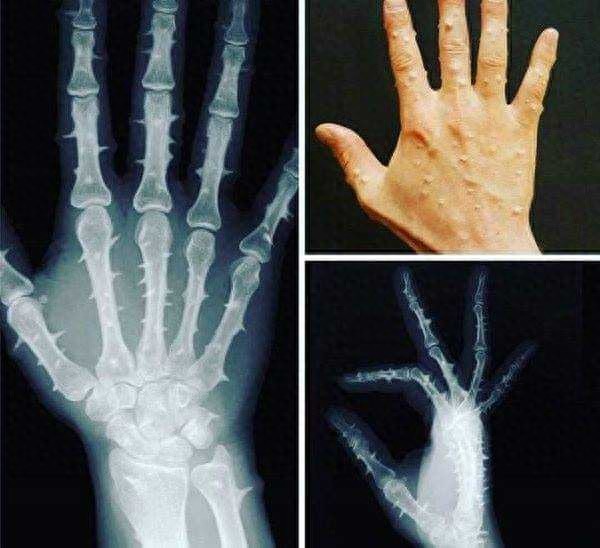

罕见的骨膜炎

骨膜炎是由于骨膜及骨膜血管扩张、充血、水肿或骨膜下出血,血肿机化,骨膜增生及炎症性改变造成的应力性骨膜损伤或化脓性细菌侵袭造成的感染性骨膜损伤。